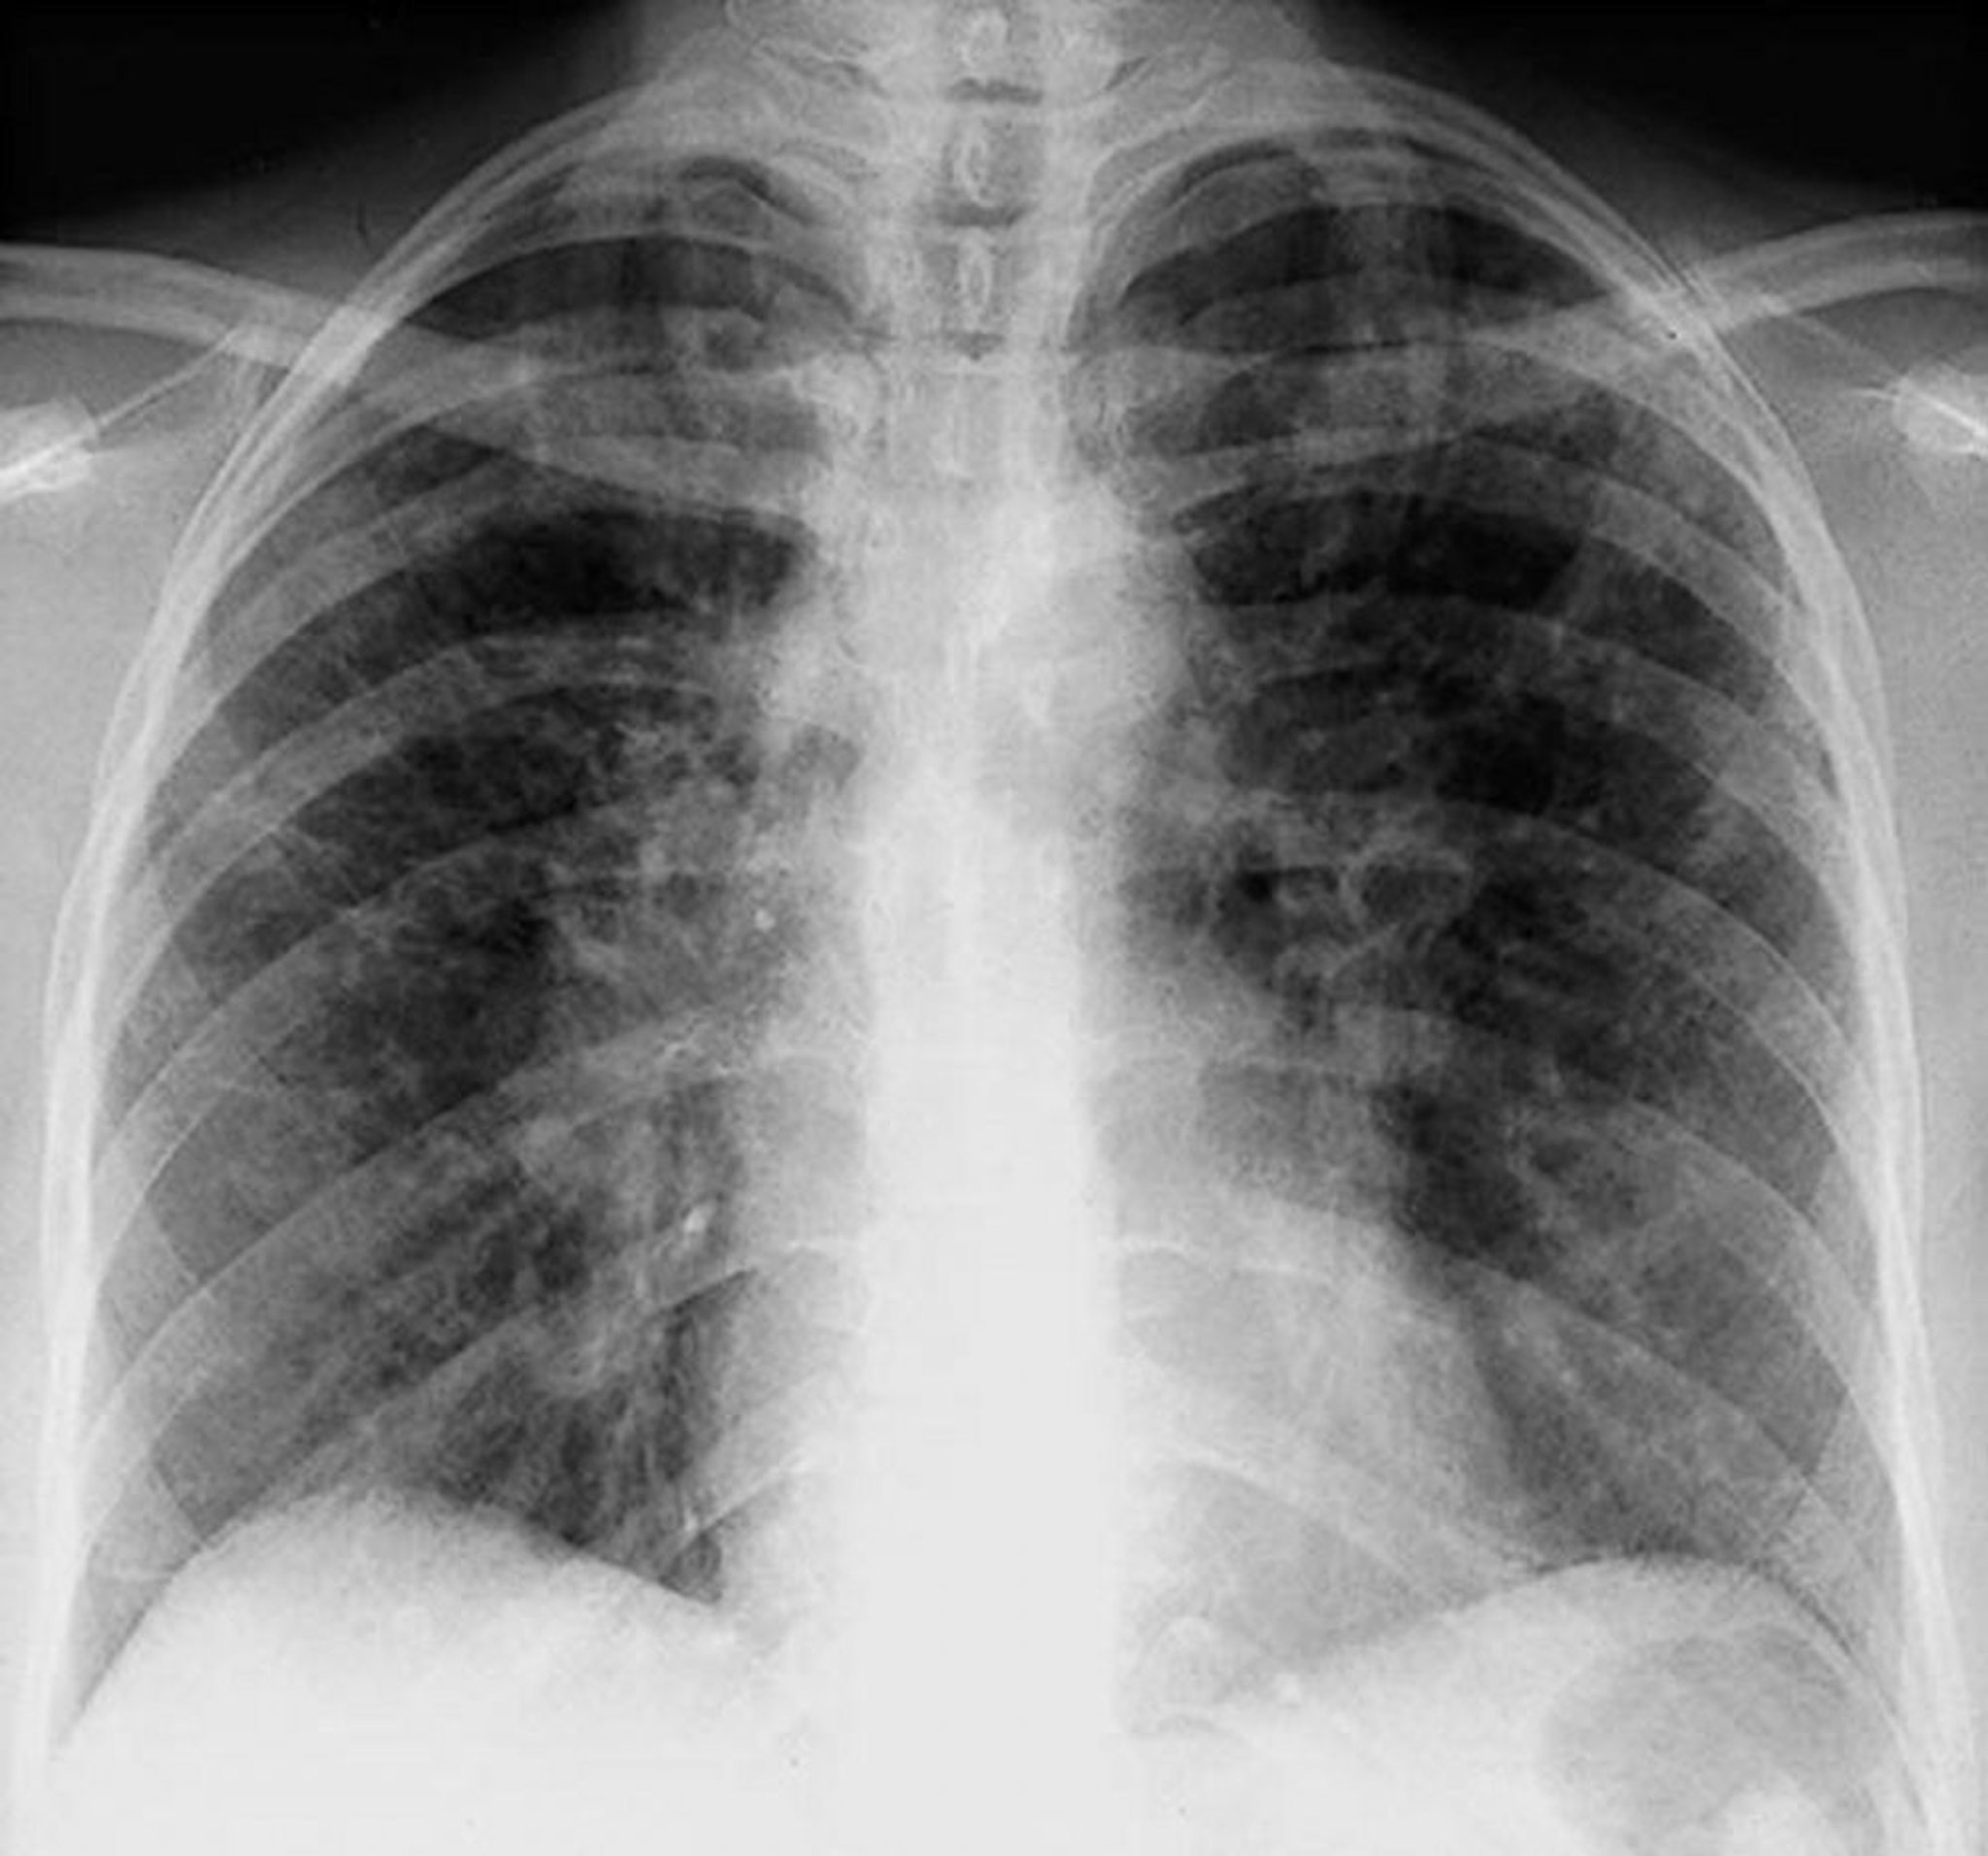

Sarcoidosis (estadio II)

Adenopatía hiliar bilateral con opacidades intersticiales en un estadio II de la sarcoidosis.

By permission of the publisher. De Tanoue L, Elias J. In Bone's Atlas of Pulmonary and Critical Care Medicine. Edited by J Crapo. Philadelphia, Current Medicine, 2005.